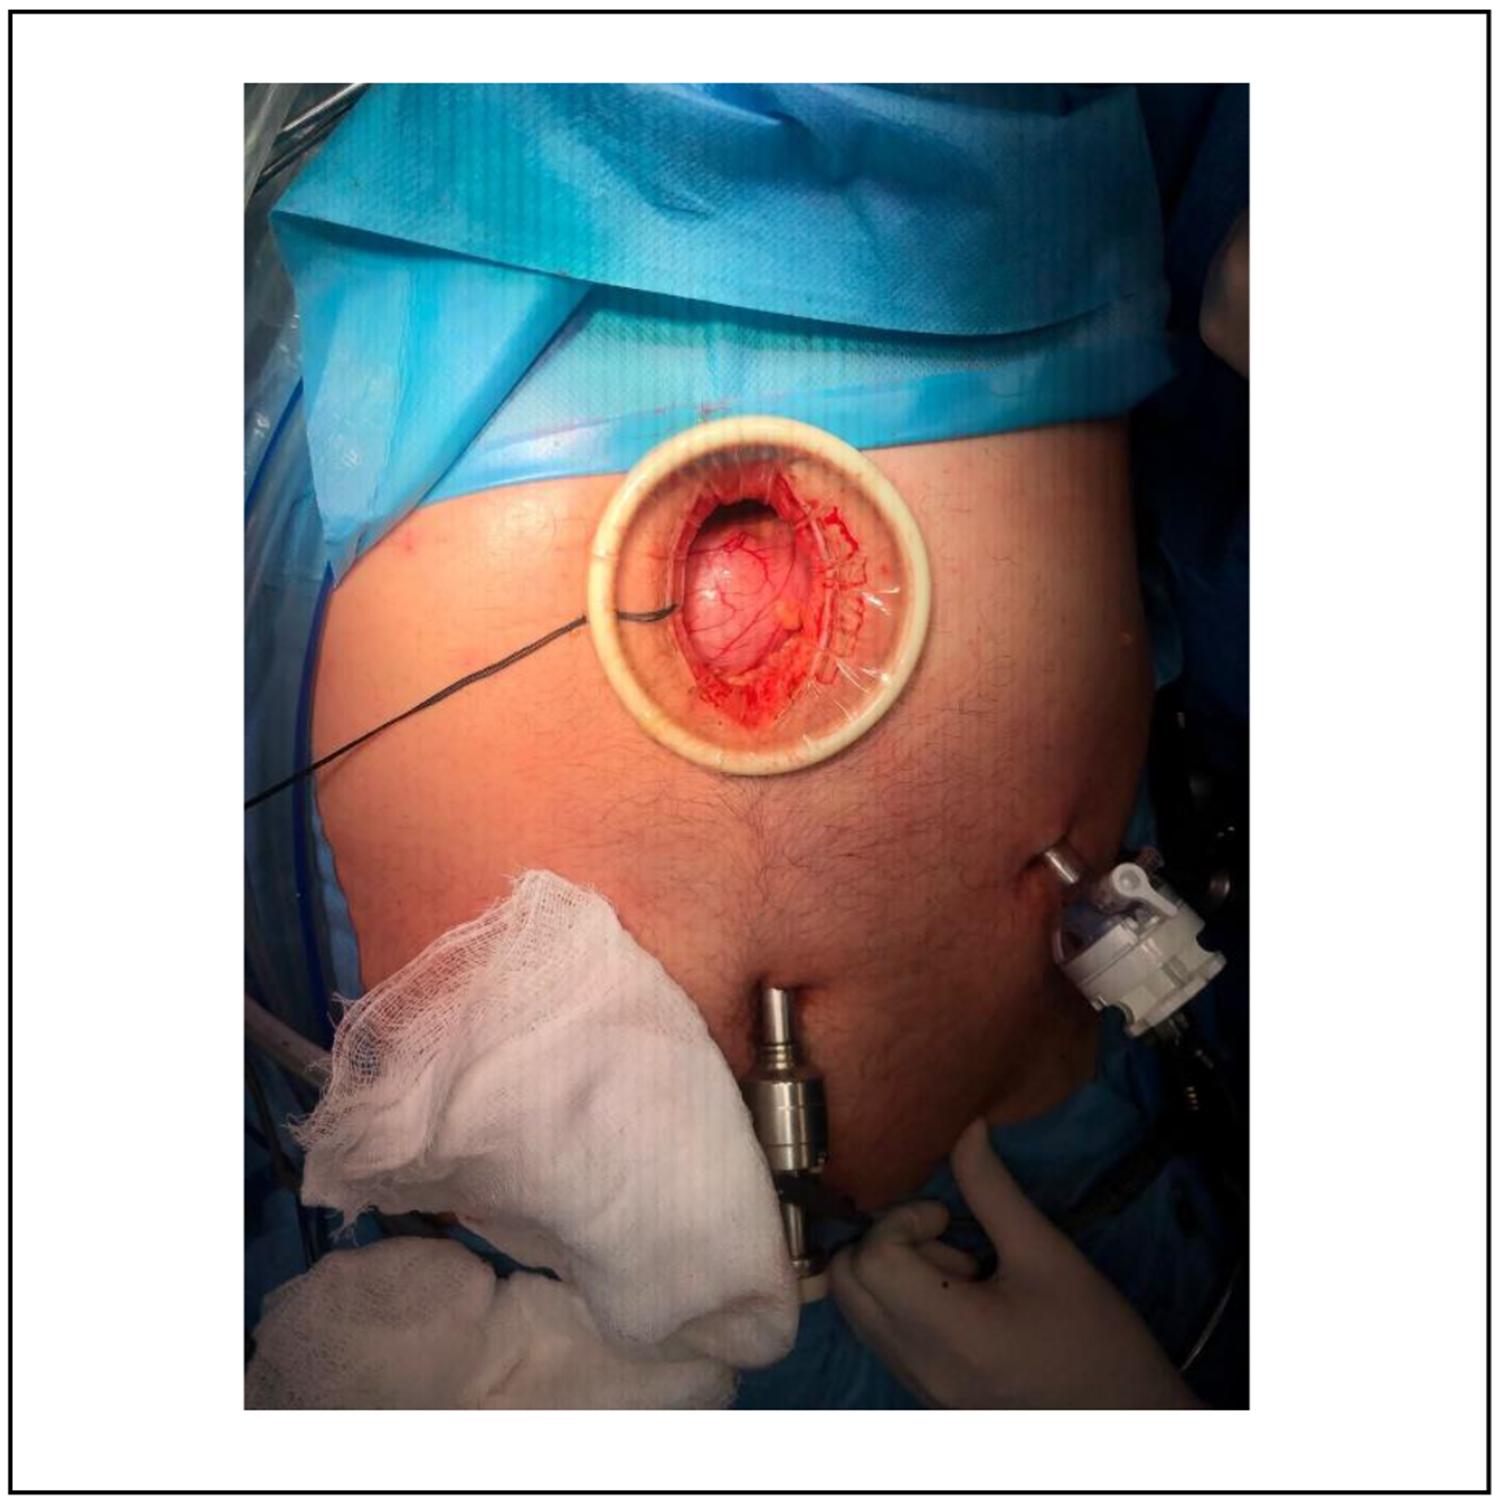

Una vez realizados los estudios se lleva a cabo la hepatectomía laparoscópica. Esta intervención requiere al paciente en posición francesa y la colocación de 4 trocares, como se muestra en la Figura 3. A partir de esto es posible explorar la cavidad e identificar un hemangioma hepático emergente. Se logró el control del pedículo vascular mediante la colocación de un lazo vascular, sin necesidad de clampeo hepático, dado que no se presentó un sangrado significativo. Posteriormente, fue posible una transección hepática con Sonicision®; se sellaron los pedículos segmentarios II y III y la vena suprahepática izquierda, mediante endograpadora vascular (dorada, 2 mm, tres líneas de grapas). Se deja drenaje de Blake enfrentado a tranche, sacado por contrabertura. Finalmente, la pieza fue retirada (Figura 4 y 5) a través de una incisión mediana supraumbilical, protegida con separador de Alexis.

Figura 5. Incisión mediana por donde se extrae la pieza, con separador de retracción y protección autoestático.